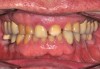

A 76-year-old, retired businessman presented to the office to improve his smile and overall oral health (Figure 1). An esthetic assessment revealed minimal display of the upper anterior teeth and dark discoloration of all teeth (Figure 2). Cephalometric analysis determined that the ANB measurement was 4°, indicating a mild Class II skeletal pattern with upright and retroclined incisors. At 145°, the interincisal angle was excessive, and at 6°, the 1-NA measurement was less than ideal (ie, 22°). If the root angulation of the upper incisors could be shifted toward the palate, it would improve the display and function of the upper anterior teeth with less restrictive anterior guidance (Figure 3).

A more comprehensive examination determined that the patient's anterior teeth bite in an end-to-end relationship with a wide area of contact, which resulted in moderate to locally severe anterior dental wear. Possible crossover bruxing with a flat lower incisor wear table was noted. In the absence of orthodontics, supraeruption of the worn teeth contributes to a poor prognosis for conservative restoration without crown lengthening and gingival reduction. Additional findings included an undersized mesial-distal width of the upper and lower anterior teeth with reduction in the dental arch perimeter; missing teeth Nos. 19 and 30 with distal drift of Nos. 20 and 21, leaving space distal of No. 22; a fixed bridge restoration for tooth No. 19 and an implant fixture in the tooth No. 30 site, both requiring repair; and some concern regarding inadequate oral hygiene.

(2.) Pre-treatment anterior bite.

Figure 2